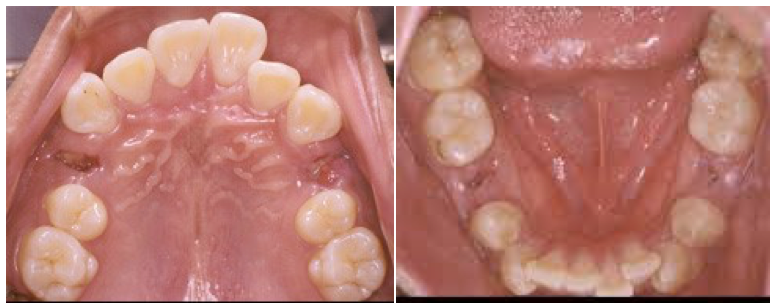

我最喜歡看到病人治療後變美變帥的樣子~~在我的治療理念中,只要你嘴唇位置不錯(聽起來好像怪怪的…有人嘴唇放錯位置嗎??!!😂 )我就會盡量利用擴大牙弓以及智齒的空間,來讓牙齒往後排列。像下面這位病人的牙齒上下極度凌亂擁擠,因外形不錯加上有智齒想要拔除,所以在設計這個案例的隱適美矯正療程時,我就選擇拔除四顆智齒,讓他的牙弓可以擴張,牙齒往兩旁擴大及後退來做排列: